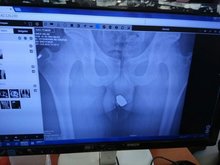

A suspected jewel thief in Konya, Turkey, has been arrested after stolen rings and necklaces were found in his rectum during an X-ray exam, police said.

The 24-year-old was taken to a local hospital to be examined by an X-ray technician, according to the Anadolu Agency.

The technician found several objects in the suspect’s rear end, including two gold rings, four gold earrings and two gold necklaces.